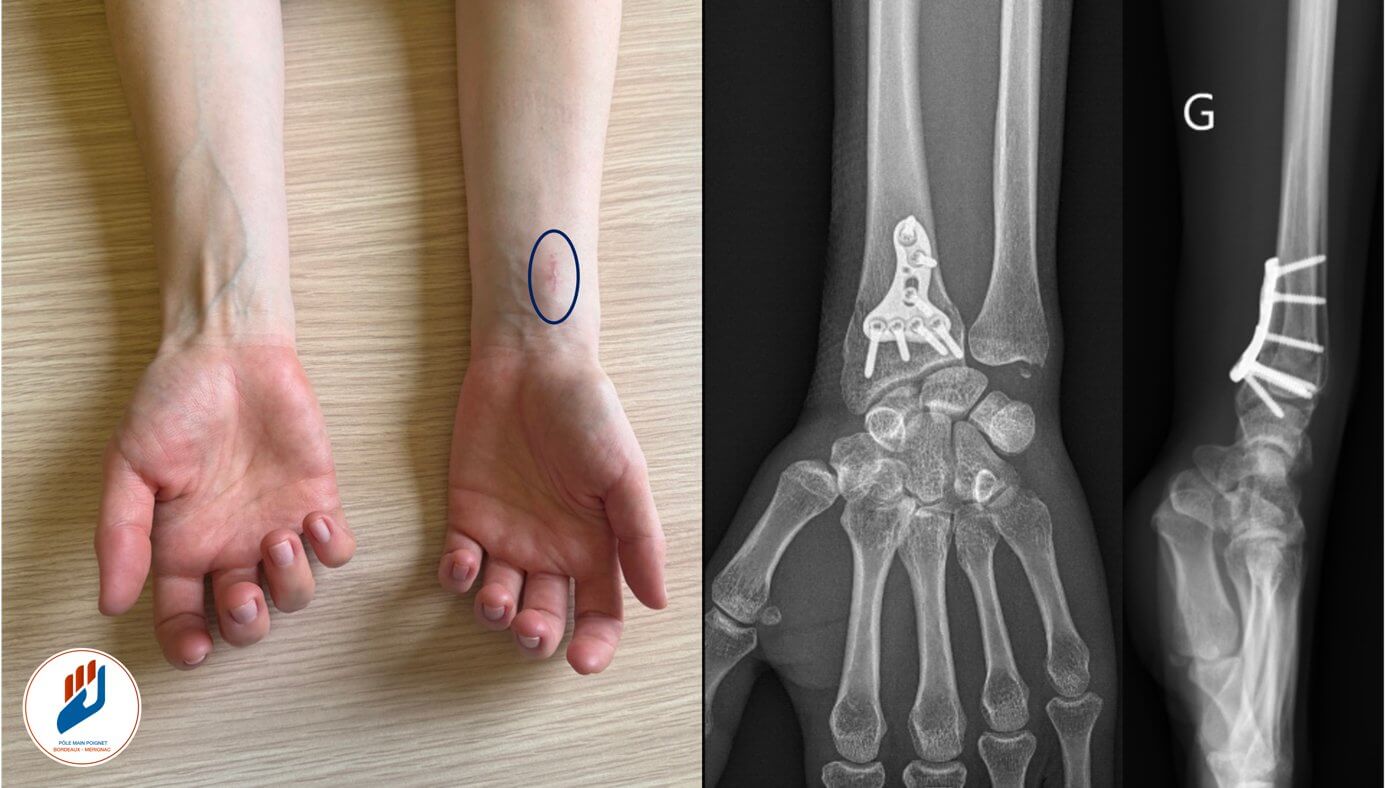

Les techniques modernes, comme l’ostéosynthèse par plaque palmaire par la méthode mini-invasive MIPO, permettent de restaurer avec précision l’anatomie articulaire afin de préserver la mobilité et la fonction du poignet.

La technique MIPO : une technique mini invasive au service du patient

MIPO signifie « Minimally Invasive Plate Osteosynthesis », soit ostéosynthèse par un abord mini-invasive. Il s’agit d’une technique chirurgicale utilisant une plaque palmaire verrouillée, mais posée en utilisant une petite incision (1,5cm) mais surtout en préservant les structure voisine de la fracture : Vascularisation, muscle…

Contrairement à l’abord classique, la technique MIPO ne nécessite pas de grande ouverture. La plaque est insérée sous les tissus (notamment le muscle carré pronateur) et glissée au contact la fracture, ce qui permet :

Des cicatrices plus discrètes

Les incisions étant limitées, les cicatrices sont petites, fines et généralement peu visibles après quelques mois.